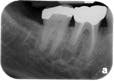

In primary endodontic disease, an acute exacerbation of a chronic apical lesion that has been caused by a necrotic pulp may result in temporary loss of alveolar bone, which can provide an avenue of drainage through the PDL into the gingival sulcus. Normally, this drainage is either not present or is seen as a sinus tract appearing in the attached gingiva. Radiographically, this condition may present as a periodontal problem, demonstrating severe bone loss. A so-called “pseudopocket” may form, with probing depths to or even past the apex of a root. The furcation of a multi-rooted tooth may also be seen to be involved (Figure 1). Diagnostically, pulp testing must be performed, specifically with thermal stimulation. A “no response” is indicative of a non-vital pulp and is diagnostic for endodontic involvement. After establishing the reason the pulp became non-vital and ruling out vertical crown and/or root fracture, conventional root canal therapy is performed (Figure 2). Removal of bacteria, bacterial by-products, and other immunogenic materials from the root canal system, followed by proper obturation, allows surrounding bone to recover and heal normally, with resolution of all periodontal pockets (Figure 3). Endodontic disease may be thought of as an “acute” process as opposed to a “chronic” process, and once the primary cause of the infection (the non-vital pulp) has been addressed and resolved, normal healing ensues.